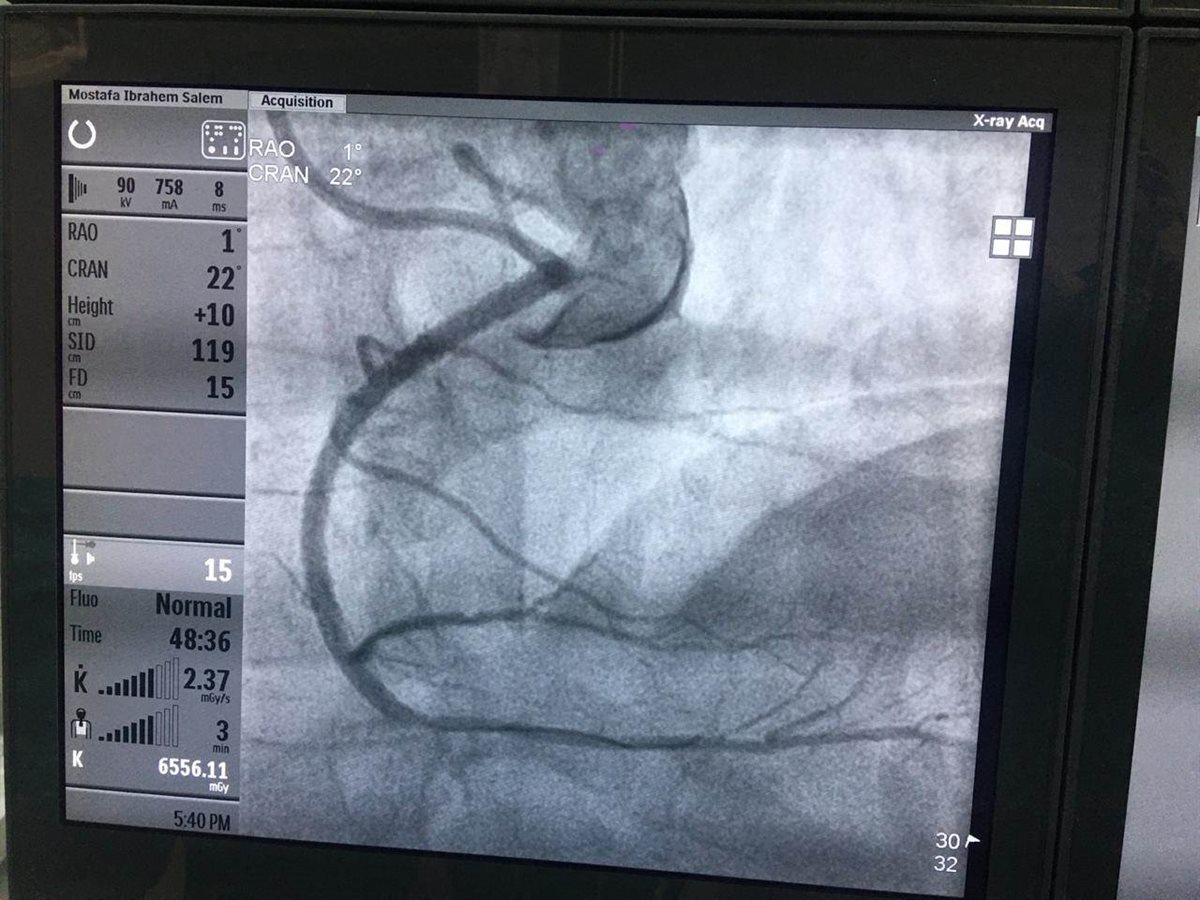

وأوضحت الهيئة، في بيان لها، اليوم، أنه تم إجراء جراحة قلب طارئة لمريض يبلغ من العمر ٦٧عام، حيث كان يعاني من انسداد شبه كلي في جزع الشريان التاجي الرئيسي الأيسر لمريض، علمًا بأن أشعة المريض كانت تشير إلى احتمال إصابته بكوفيد 19 ، ولكن كان لابد من إجراء العملية رغم كل الاحتمالات حتى لا يودي الانتظار بحياة المريض إلى الخطر، وتم إجراء جراحة عاجلة لإنقاذ المريض بنجاح على يد أ.د طارق رشيد "خبير القسطرة القلبية"، أ.د. أحمد شبل "استشاري القلب والقسطرة التداخلية" وفريقهم الطبي المعاون، وبعد إجراء العملية تم التأكد من إصابته "كوفيد ١٩"، فيما يتم متابعة حالة المريض الصحية ، وهو الآن بحالة جيدة.

ولفت د. قطب السيد "مدير مستشفى النصر التخصصي ببورسعيد"، إلى نجاح فريق قسطرة القلب بمستشفى النصر التخصصي التابع للهيئة العامة للرعاية الصحية في إجراء ٦ عمليات قسطرة دقيقة ومعقدة لمرضى الانسداد التام المزمن للشرايين التاجية CTO من منتفعي منظومة التأمين الصحي الشامل، أجرى العمليات الأستاذ الدكتور طارق رشيد خبير القسطرة القلبية، و استشاري القلب بمجموعة مستشفيات كليوباترا ، بمعاونة الأستاذ الدكتور أحمد شبل استشاري القلب والقسطرة التداخلية وفريقهم الطبي المعاون، مشيرًا إلى تواجد أ.د. طارق رشيد بالمستشفى بشكل منتظم لمناظرة حالات الانسداد المزمن للشرايين التاجية، الأمر الذي يوفر عناء السفر ومشقة انتقال المنتفعين بمنظومة التأمين الصحي الشامل خارج المحافظة للحصول على الخدمة الطبية.